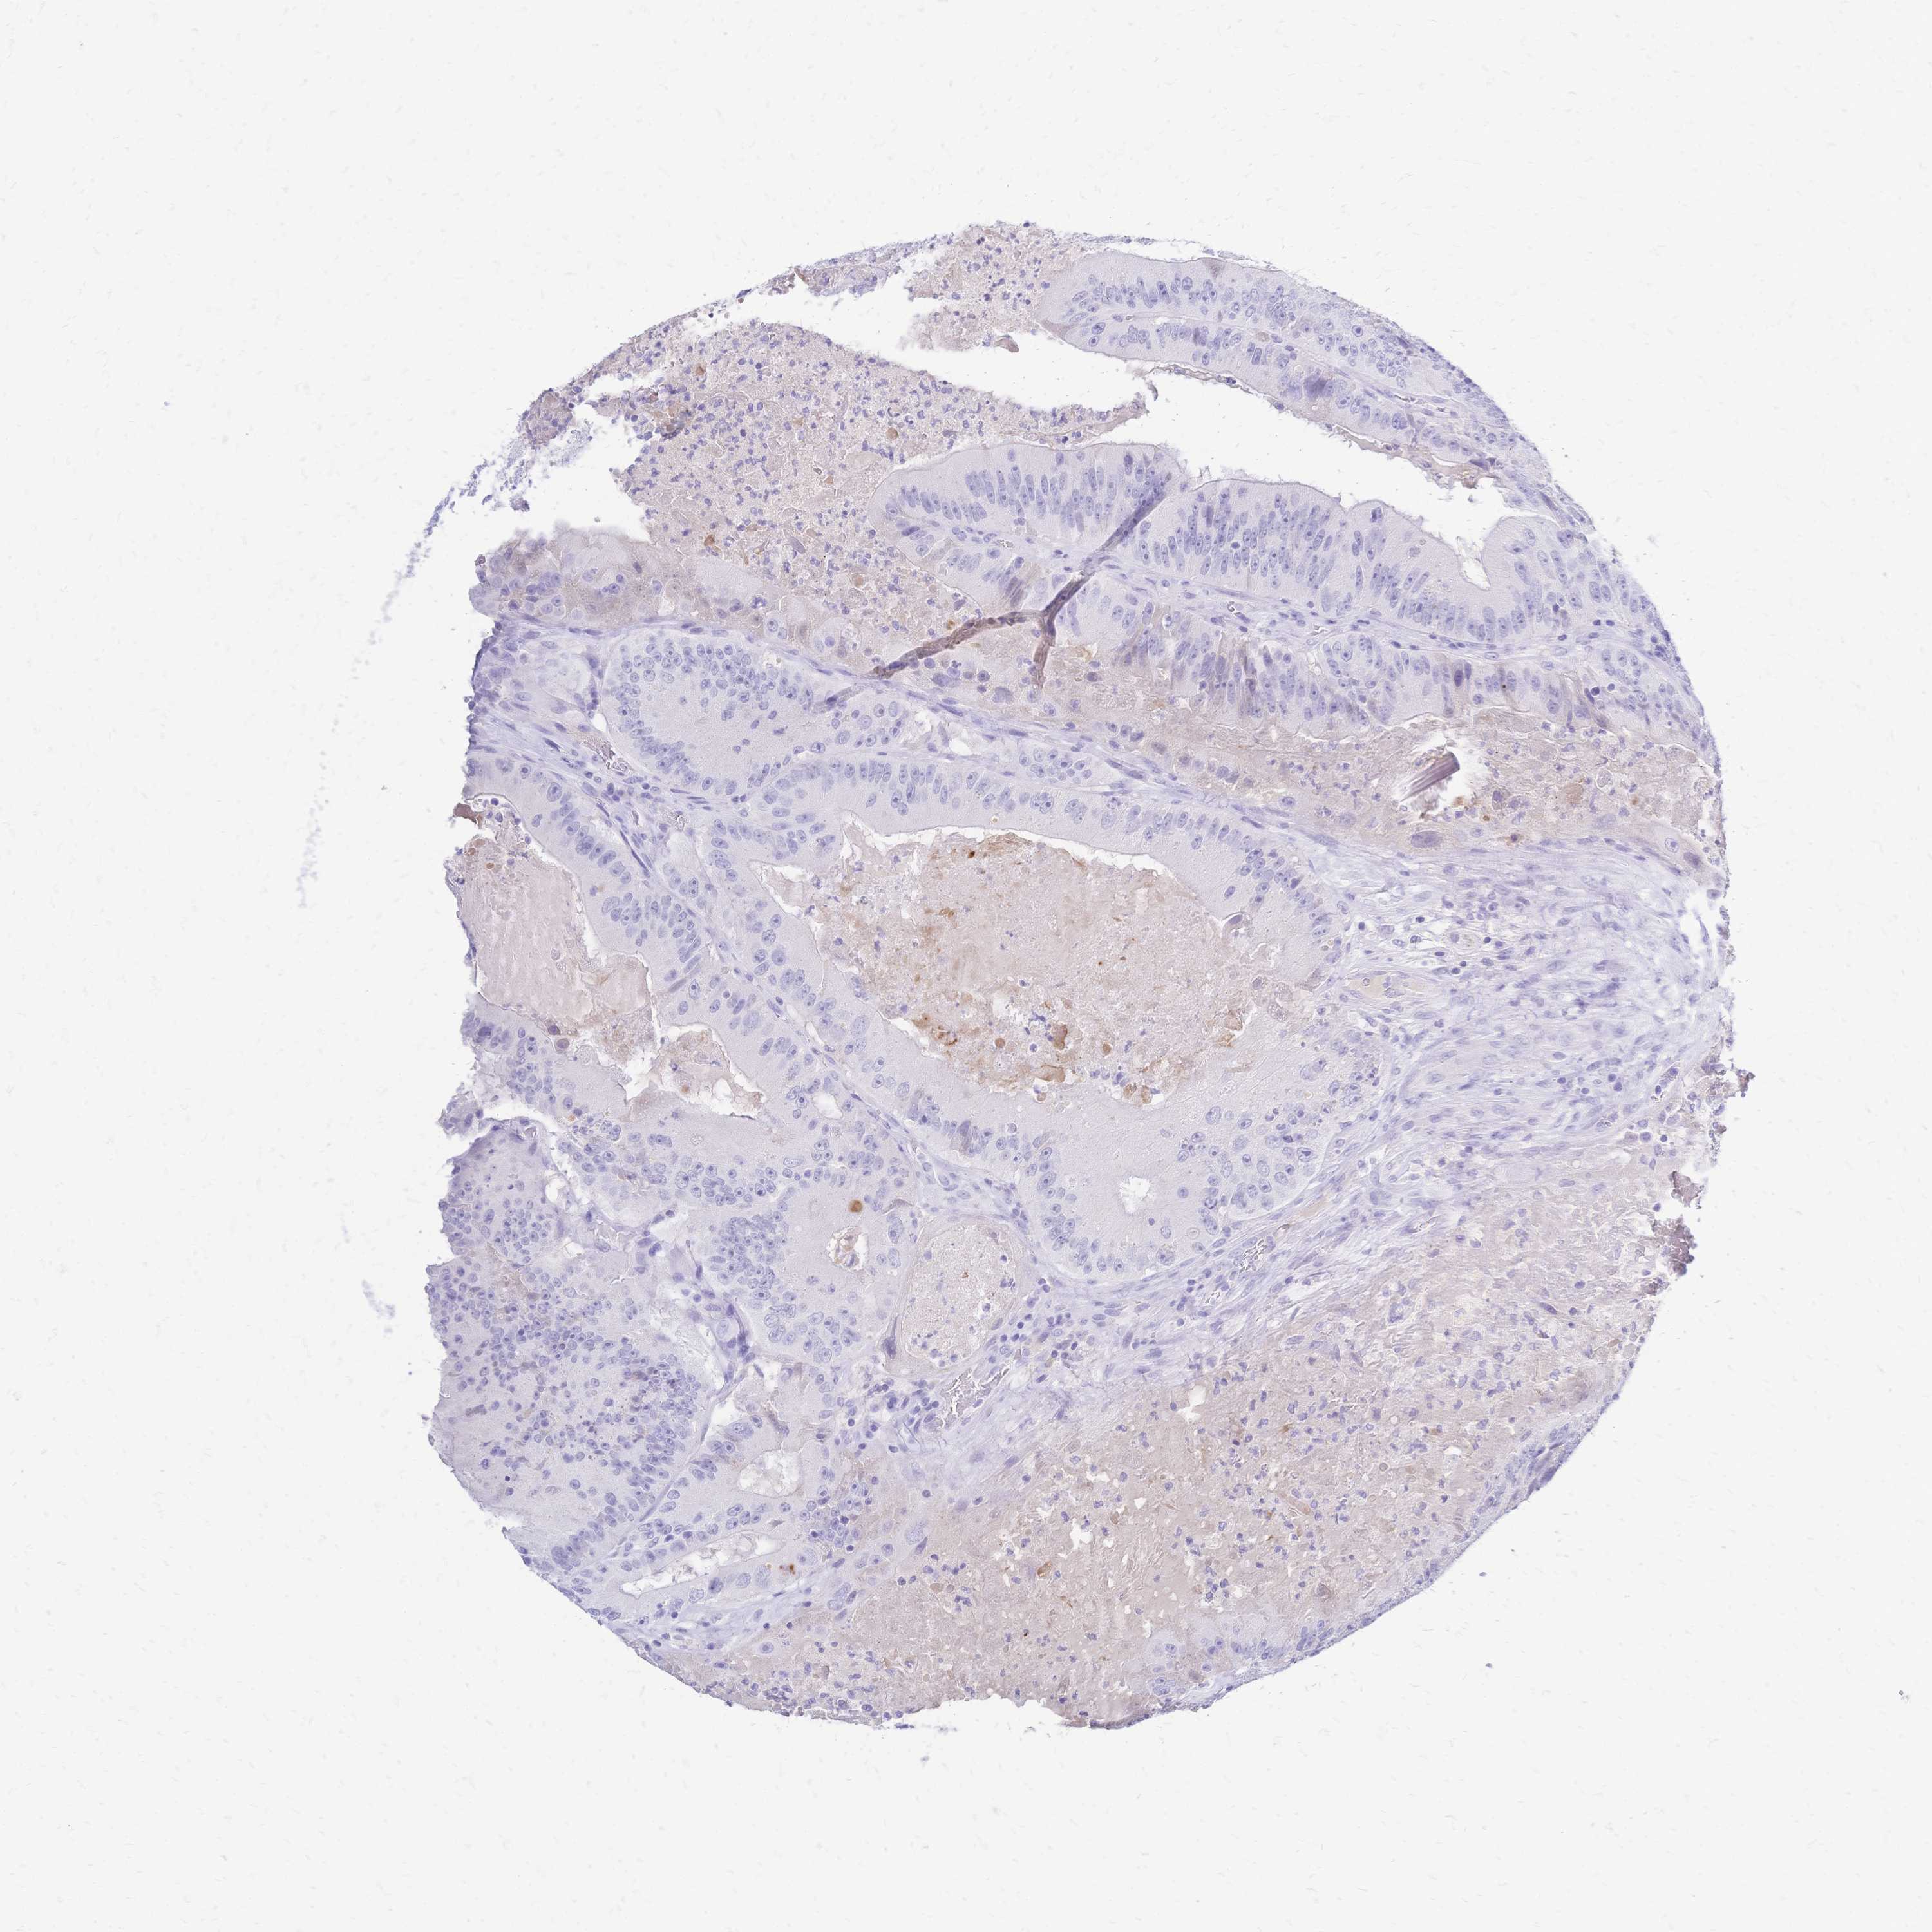

CANCER COLORECTAL CANCER Show tissue menu

Colorectal cancer

Human cancer

Colon adenocarcinoma